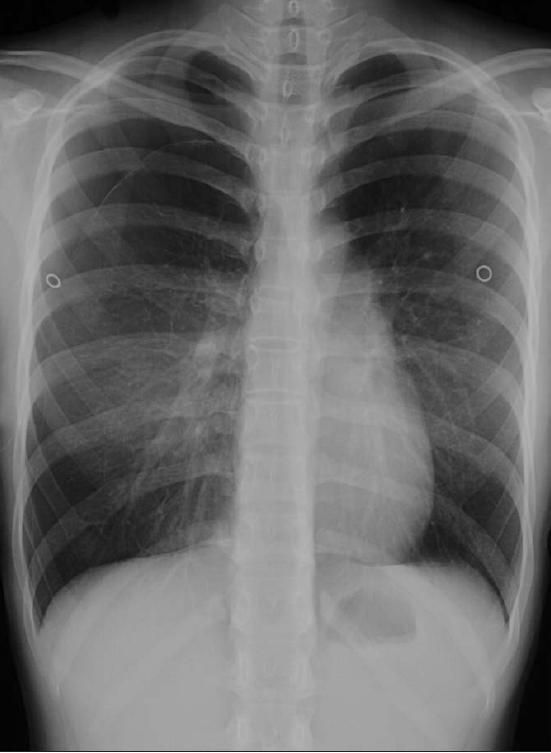

The patient's chest radiograph is shown.

The chest radiograph shows a moderate pneumothorax on the right (Figure 1).

The presence of pneumothorax is usually confirmed by plain chest radiographs. A visceral pleural line without vessel markings is a key diagnostic finding.3 Radiographs may also show hyperlucency of vascular and lung markings. Chest CT can help distinguish preexisting lung conditions, such as neoplastic disease, from spontaneous pneumothorax when the diagnosis is uncertain.2,4

In this patient, a pigtail catheter was used to aspirate air from the pleural cavity; serial chest radiographs performed over the following days showed gradual lung re expansion (Figure 2). She was discharged after 7 days and was scheduled for follow-up with her primary care physician.